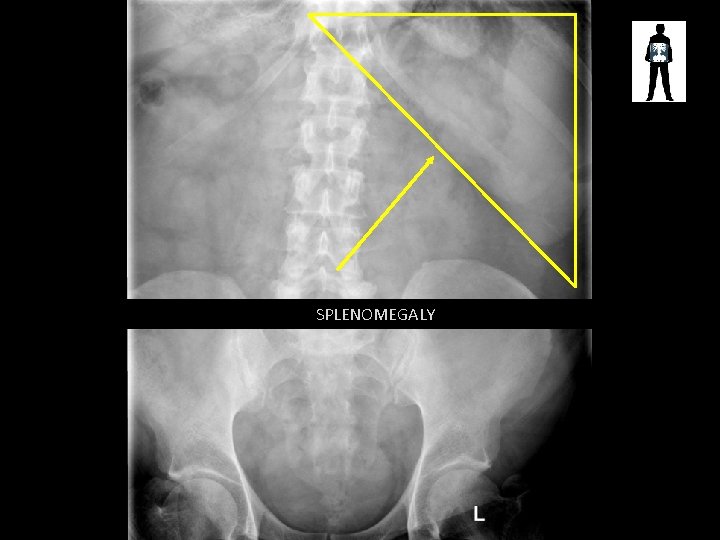

SPLENOMEGALY

Splenomegaly • Spleen enlarges slightly in normal function – however major enlargement may be caused by: – Dealing with major infection – Trauma – Tumours • Increased risk of rupture and major blood loss